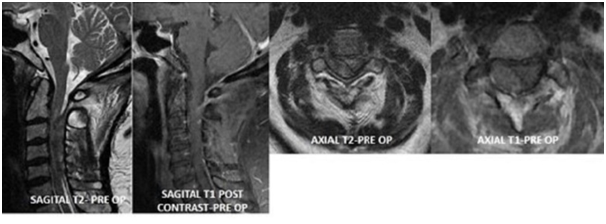

A 69 year old right handed female presents to ER with sudden onset right sided weakness. She had past medical history of diabetes mellitus, hypertension, hyperlipidemia and obesity. She developed right upper and lower extremity weakness which progressed by the time she presented to ER and she was unable to move her right side. She presented within 90 minutes and was initially examined by ER Physician within a minute of her presentation, stroke code (as per hospital's ischemic stroke guideline) was activated which lead to urgent CT Brain within 15 minutes and was examined by Neurologist within 30 minutes of her presentation. Quick history and collateral history, excluding the relative and absolute contraindications, neurologist noted she had right sided neck pain and had right sided hemiplegia. Neurologic examination at this stage showed she had flattened right naso-labial fold, right upper extremity power was 0/5 and right lower extremity was 0/5, without any sensory loss. She had absent reflexes all over and reduced tone and planters was extensor on the right and was flexor on the left side. Her NIHSS (National Institute of Health Stroke Scale) was 9. As initial CT brain was unremarkable, her family was consented for Fibrinolytic therapy with IV rtPA (recombinant tissue Plasminogen Activator) and was dispensed at a dose of 0.9mg/kg within 45 minutes of her presentation. While in the transit from ER to Stroke Unit that is within 3 hours post her IV rtPA, she started to complain that she can't feel her left leg and arm and has developed left sided weakness. This prompted a repeat CT brain which was unremarkable for any signs of hemorrhage and or ischemia. Re-examination at this stage showed she had quadraparesis, with dense right hemiplegia of power 0/5 in the right upper and lower extremity and also left hemiparesis with power 1/5 in the left lower extremity and 2/5 in the left upper extremity with reduced tone all over and absent reflexes. Her Babinski's response was extensor on the right side and was unequivocal on the left side. She also had left hemi-sensory loss to pinprick and temperature sense up to her neck sparing the face along with right horner's (ptosis, smaller pupil and enopthalmos) with preserved extra ocular movements. Her neck pain had worsened and has been requiring opioid analgesics, with new development of her symptoms and signs this lead to further neuroimaging in the form of MRI Brain Stroke Protocol which was unremarkable and MRI Cervical spine which showed spindle-shaped extradural lesion extending from C2 to C6 exerting significant mass effect on the thecal sac and related spinal cord with subsequent cord edema. The lesion predominantly is of low signal in T2 and intermediate signal in T1 displaying tiny foci of enhancement after administration of contrast, suggesting underlying tumor with a surrounding hematoma, Figure 1. Emergent neurosurgical evaluation prompted urgent cervical decompression in the form of right hemi-laminectomy from C2 to C5 which revealed extra-dural tumor with clotted hematoma which was sub- acute, compressing the spinal cord this was excised, Figure 2, and with resultant improvement in her left sided motor function, she remained weak on the right side and has been treated with IV dexamethasone and with aggressive physiotherapy. This case highlights usual presentation with a rarest reason mimicking stroke.

Figure 1 Pre-Operative; MRI of Cervical Spine with and without contrast showed spindle-shaped extradural lesion extending from C2 to C6 exerting significant mass effect on the thecal sac and related spinal cord with subsequent cord edema. The lesion predominantly is of low signal in T2 and intermediate signal in T1 displaying tiny foci of enhancement after administration of contrast.